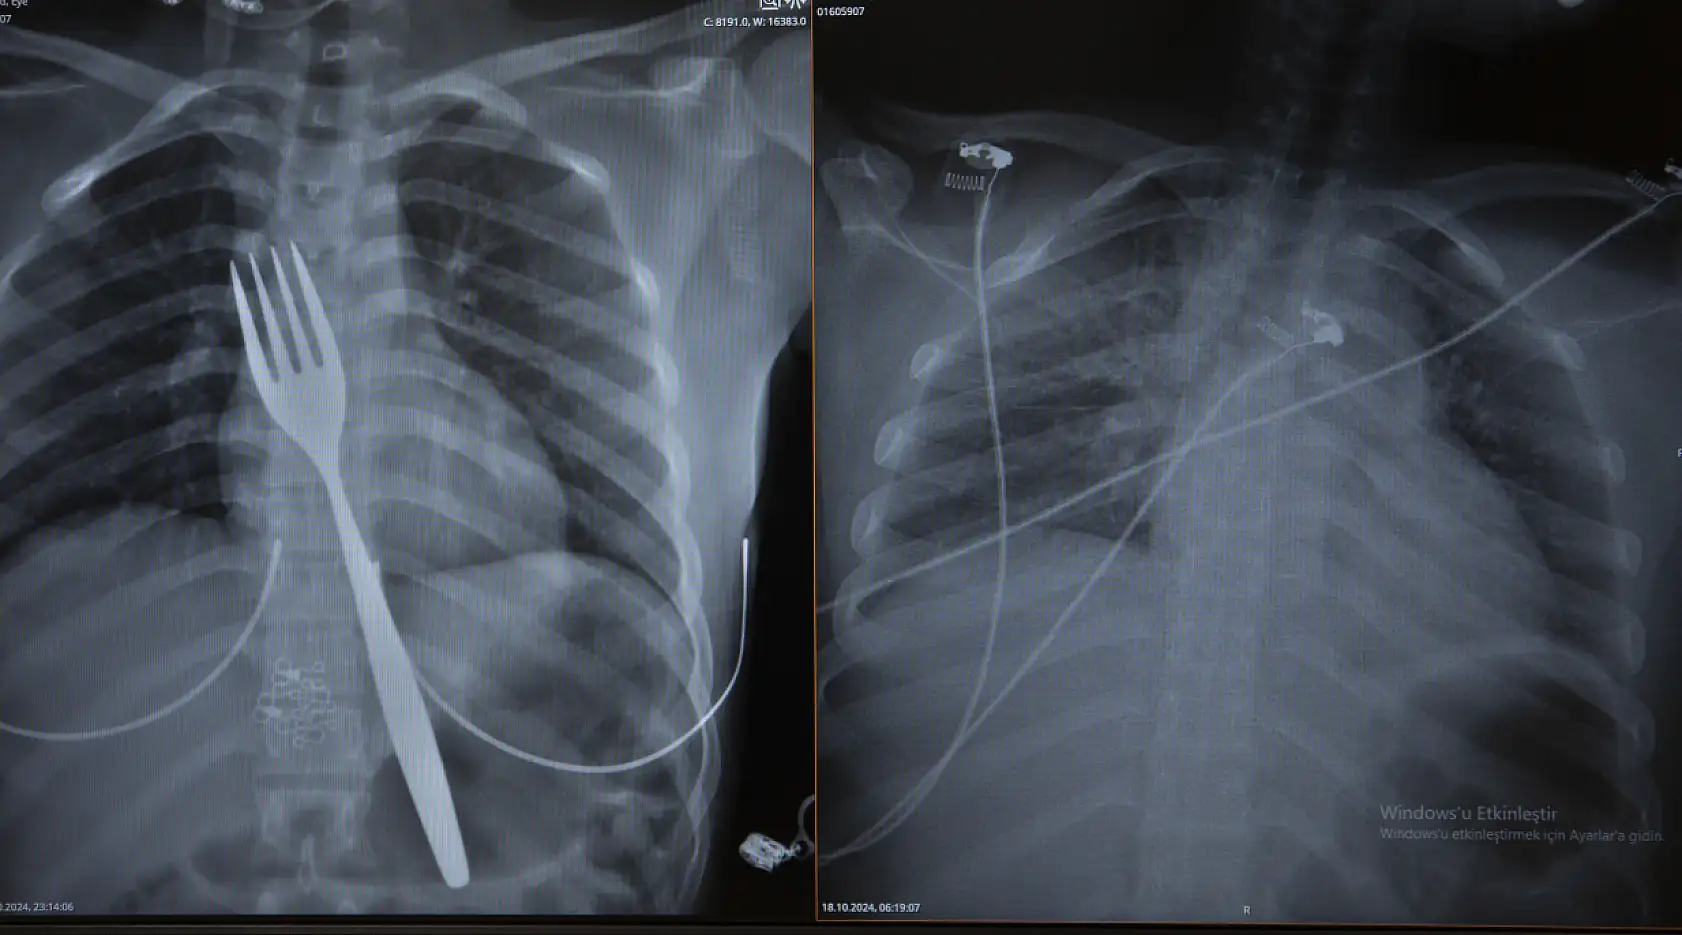

- Hastaneye kaldırılan genç kızın yemek borusundaki çatal, mide ameliyatıyla çıkarıldı

Hastaneye kaldırılan genç kızın yemek borusundaki çatal, mide ameliyatıyla çıkarıldı

Genç kızın yuttuğu çatal, operasyonla alındı.

çatal yutan genç kız